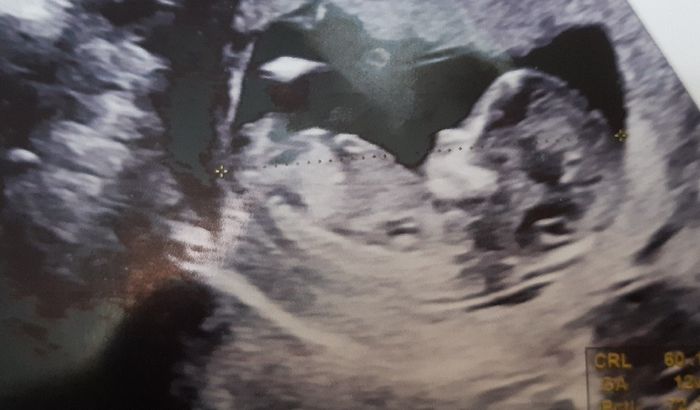

Ciao mamme e future mamme! Questa Pasqua ci porterà un altro Pulcino. Sono già mamma di Jacopo di un anno e l’anno prossimo saremo in 4. Chi altra mamma di aprile? ❤️